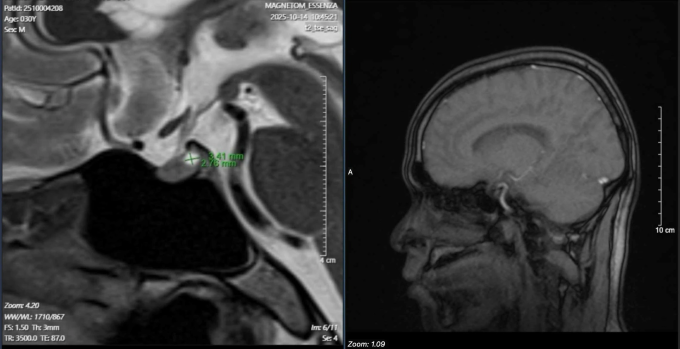

Kết quả xét nghiệm thấy nồng độ hormone prolactin trong máu tăng cao bất thường – dấu hiệu tuyến yên đang bị rối loạn hoạt động. Dựa trên kinh nghiệm lâm sàng, bác sĩ Lực tư vấn chụp MRI tuyến yên, kết quả xác nhận bệnh nhân có u tuyến yên. Khối u lành tính nằm ngay vùng não nhưng đang “khống chế” toàn bộ hệ sinh dục, gây tăng tiết hormone prolactin, ức chế trục nội tiết quan trọng, dẫn đến suy giảm ham muốn và rối loạn cương dai dẳng.

Hình ảnh khối y tuyến yên của bệnh nhân. Ảnh: Bác sĩ cung cấp